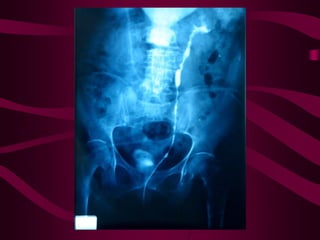

Este documento describe la tuberculosis genitourinaria. Afecta más a hombres que a mujeres. Se transmite principalmente a través de la infección pulmonar primaria y luego se disemina a través de la sangre a los riñones u otros órganos. Causa lesiones como granulomas y necrosis si no se controla, lo que puede provocar complicaciones como abscesos e insuficiencia renal. Se diagnostica mediante pruebas de orina y tratamiento con medicamentos durante varios meses.